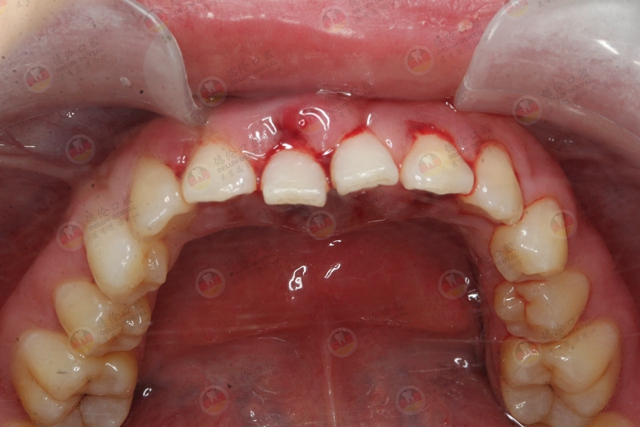

刚刚出现的是牙周病的前身:牙龈炎,它的到来意味着我们会时不时牙龈出血,慢慢地牙龈会出现轻微的红肿。

而发展成牙周病后,带来的就不是简简单单的牙龈出血了。随后,长期的牙龈红肿,出血,牙龈萎缩,牙槽骨吸收,牙龈溢脓,牙齿松动,然后就是完好无缺的牙齿,却慢慢脱落了。